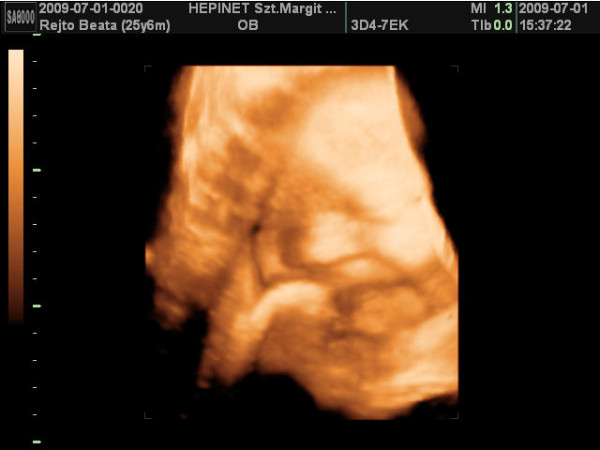

ma vagyok 6 hetes 5 napos.a jó hír,hogy szombaton már láttam és hallottam életemben először a kicsi szívhangját!!!!!!![]()